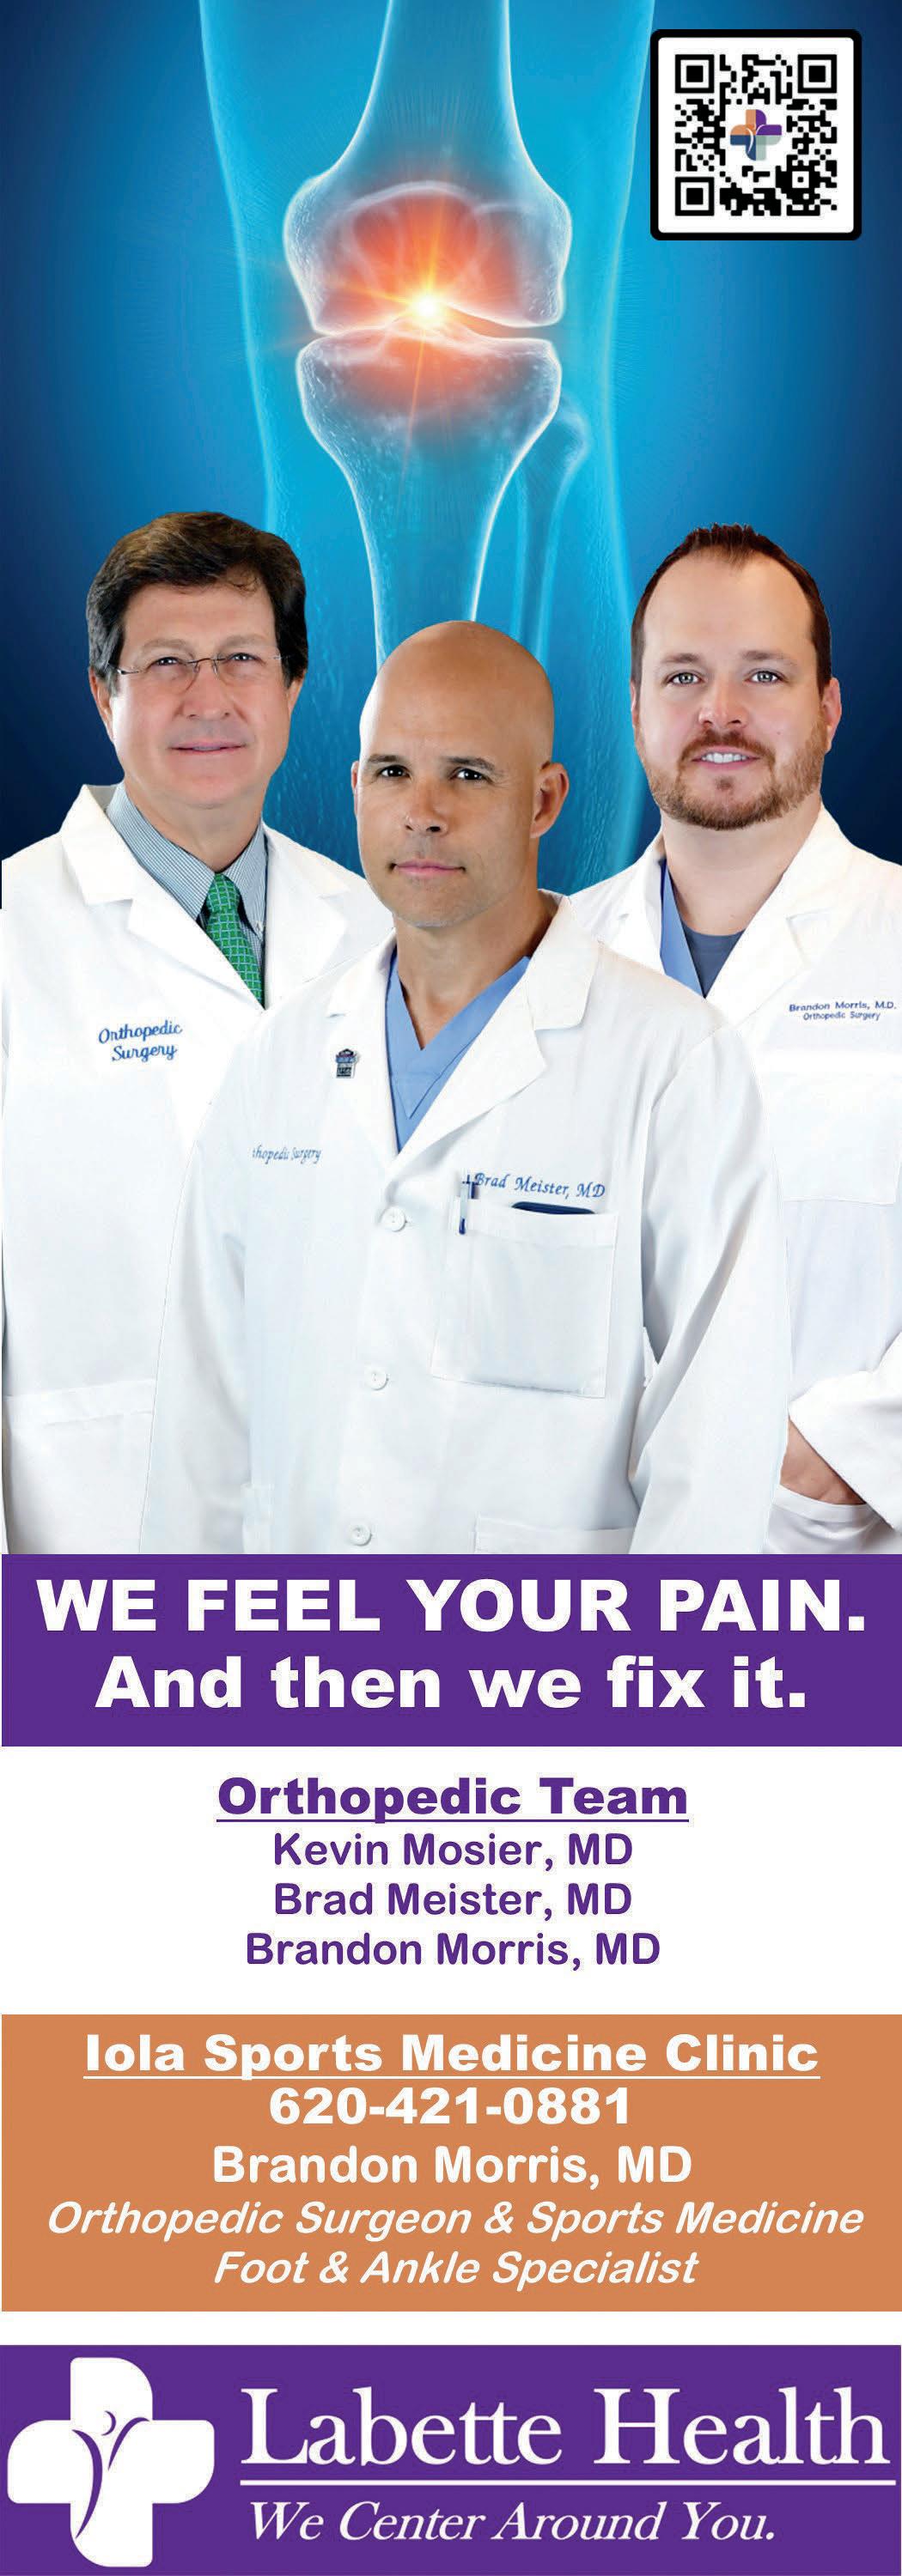

4 BUILDING & CONSTRUCTION Advanced Systems Homes 13 Cleaver Farm & Home . . . . . . . . . . . . . . . . . . . . . . . . . 14 D&M Mini Barns 16 Hofer & Hofer 16 Korte Construction & Remodel 16 Nelson Quarries 16 New Klein Lumber Co . . . . . . . . . . . . . . . . . . . . . . . . . . 15 Quality Structures 17 Yutzy Custom Structures . . . . . . . . . . . . . . . . . . . . . . . 13 EDUCATION & CHILDCARE Allen Community College 17 The Growing Place 19 Kids Kingdom of Iola 17 USD 257 . . . . . . . . . . . . . . . . . . . . . . . . . . . . . . . . . . . 18 USD 258 19 FARM AGChoice . . . . . . . . . . . . . . . . . . . . . . . . . . . . . . . . . . 19 Bluestem Farm & Ranch Supply 20 Green Cover Seed 20 Mid-West Fertilizer 20 PrairieLand Partners . . . . . . . . . . . . . . . . . . . . . . . . . . 19 Red Barn Veterinary Service . . . . . . . . . . . . . . . . . . . . 20 SoilMaxx 21 FOOD & DRINK A&W All American Food 22 Derryberry Breadery 23 El Charro . . . . . . . . . . . . . . . . . . . . . . . . . . . . . . . . . . . 23 Fillmore Coffeehouse + Plant Café . . . . . . . . . . . . . . . 21 G&W Foods of Iola 63 Honeybee Bruncherie 21 Marmaton Market 23 Mildred Store . . . . . . . . . . . . . . . . . . . . . . . . . . . . . . . . 23 Moran Locker 23 O’Shaughnessy Liquor 24 Our Market 24 Sam & Louie’s Italian Restaurant 24 Sharky’s Pub & Grub of Iola . . . . . . . . . . . . . . . . . . . . 24 Sonic Drive-In 24 FUEL D&D Propane . . . . . . . . . . . . . . . . . . . . . . . . . . . . . . . 25 Pump ‘N Pete’s 25 HEALTHCARE Allen County Regional Hospital-Saint Luke’s Health System 2 Blanket Fort Therapy 30 Community Health Center of Southeast Kansas . . . . . 25 GoodLife Innovations 27 Iola Pharmacy 28 Iola Vision Source 27 Labette Health . . . . . . . . . . . . . . . . . . . . . . . . . . . . 32, 33 Neosho Memorial Regional Medical Center 28 Ryan Coffield D.D.S., P.A. 30 Southeast Kansas Mental Health Center 26 Southeast Kansas Multi-County Health Depts 29 Tri-Valley Developmental Center . . . . . . . . . . . . . . . . . 29 Yates Center Dental and Orthodontics 30 The Wellness Studio 30

32

33